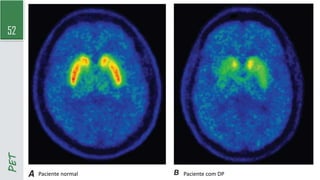

TC por emissão de pósitrons (PET) com FGD

- Mais preciso que o SPET cerebral (mas pouco disponível)

- Mostra alterações metabólicas no cérebro dos pacientes com DP

PET

Paciente normal Paciente com DP